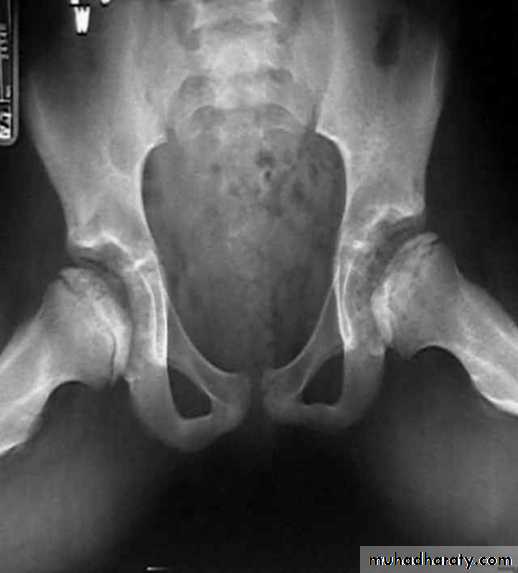

ANKYLOSING SPONDYLITIS (AS)

Seronegative spondyloarthropathy of the axial skeleton and proximal large joints.

Clinical: males >> females. HLA-B27 in 95%. Insiduous onset of back pain and stiffness. Onset: 20 years.Radiographic features:

* SI joint is the initial site of involvement:

bilateral, symmetrical

Erosions: early ,Sclerosis: intermediate , ankylosis: late

* Contiguous thoracolumbar involvement

Vertebral body "squaring": early osteitis

* Syndesmophytes

* Bamboo spine: late fusion and Bamboo spine

ligamentous ossification

*ankylosed spine (fracture)

* Enthesopathy is common(("whiskering of tuberosities )

* Arthritis of proximal joints (hip > shoulder) in 50% ,erosions and osteophytes